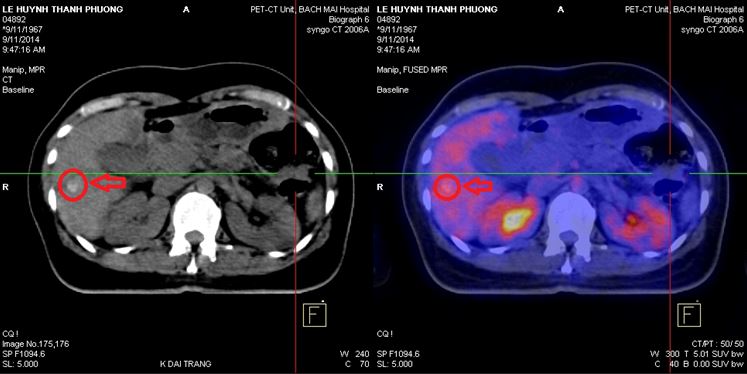

Chụp PET/CT :

- Trong nhu mô gan có nhiều khối tăng hấp thu F-18 FDG, khối lớn nhất hạ phân thùy VII, max SUV=9,1 (kích thước 3,3x4,7x3,6cm), các khối khác, max SUV=4,59 (kích thước 2,7x3,5x3,0cm), max SUV=3,2 (kích thước 2,6x2,9x2,8cm)

- Đại tràng góc lách có khối kích thước 5,2x6,8x6,7cm, làm hẹp lòng đại tràng, tăng hấp thu F-18 FDG, max SUV=12,1

Hình 1,2,3: Hình ảnh chụp PET/CT toàn thân: Vòng tròn đỏ là tổn thương tăng hấp thu F-18 FDG tại u gan và vòng tròn vàng là hình ảnh khối u đại tràng góc lách